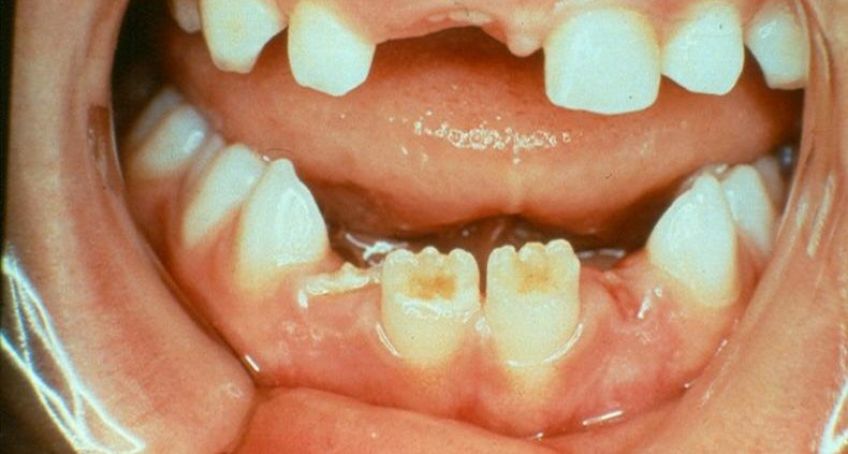

دندان ها نامنظم و تغییر رنگ یافته هستند و مینا و عاج نازک و نامنظم هستند

رنگ این دندان ها قهواه ای متمایل به زرد است

این اختلال در اثر وقفه در تکامل دندان و اغلب در یک قوس از فک دیده شده است.در بعضی از موارد ممکن است دندان های دائمی فضای دندان های شیری نرمال را پر کنند.دندان های درگیر به شکل غیر طبیعی رویش کرده و سطح آنها بسیار زبر و خشن هستند.به دلیل اختلال ساختمانی دندان های مبتلا بسیار مستعد پوسیدگی می شوند و با کمترین ضربه دچار شکستگی می شوند.وجود چرک در لثه هم از دیگر یافته های شایع دراین بیماری است.عفونت ها و آبسه های عود کننده نیز حتی در مواردی که پوسیدگی های وسیع وجود ندارد دیده می شود.